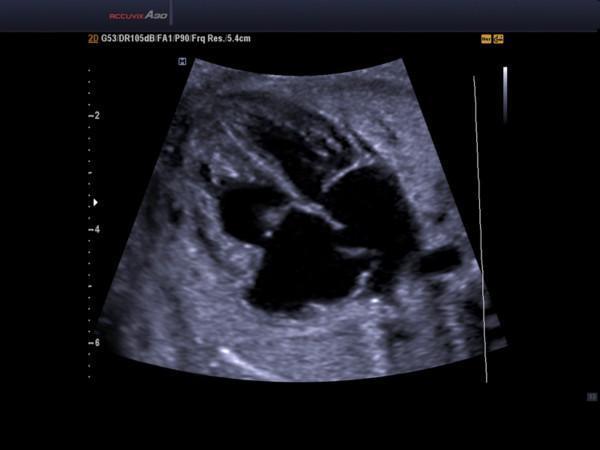

醫(yī)學(xué)超聲波檢查作為一種常規(guī)的檢查手段,已經(jīng)廣泛的應(yīng)用在臨床。它的工作原理與聲納有一定的相似性,即將超聲波發(fā)射到人體內(nèi),當(dāng)它在體內(nèi)遇到界面時(shí)會(huì)發(fā)生反射及折射,并且在人體組織中可能被吸收而衰減。

因?yàn)槿梭w各種組織的形態(tài)與結(jié)構(gòu)是不相同的,因此其反射與折射以及吸收超聲波的程度也就不同,醫(yī)生們正是通過(guò)儀器所反映出的波型、曲線(xiàn),或影象的特征來(lái)辨別它們。

超聲診斷儀在臨床上應(yīng)用最廣的是B型超聲和D型超聲,即人們通常所說(shuō)的B超和多普勒超聲。由于超聲具有無(wú)創(chuàng)、高靈敏度、應(yīng)用面廣、低成本和操作方便等優(yōu)點(diǎn),被廣泛應(yīng)用于臨床診斷,尤其是胸部臟器、心臟、眼科和婦產(chǎn)科的診斷。